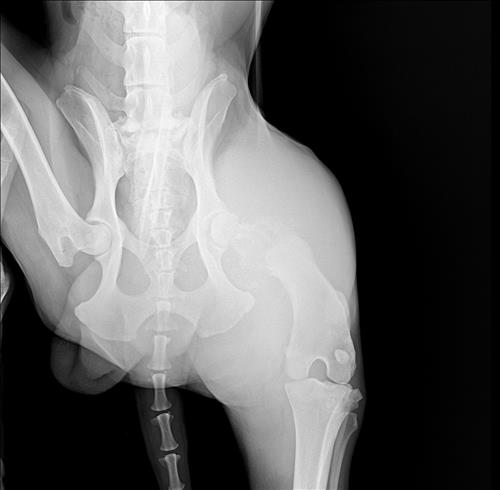

골육종 진단받았는대 맞을까요

엑스레이 상으로 이정도면 전의가망성이 높고 나이도 나이고 대형견이고 맛있는거 많이주고 마음에. 준비를하라고 하는대 다른선생님 의견도 들어보려고 문의 드립니다.